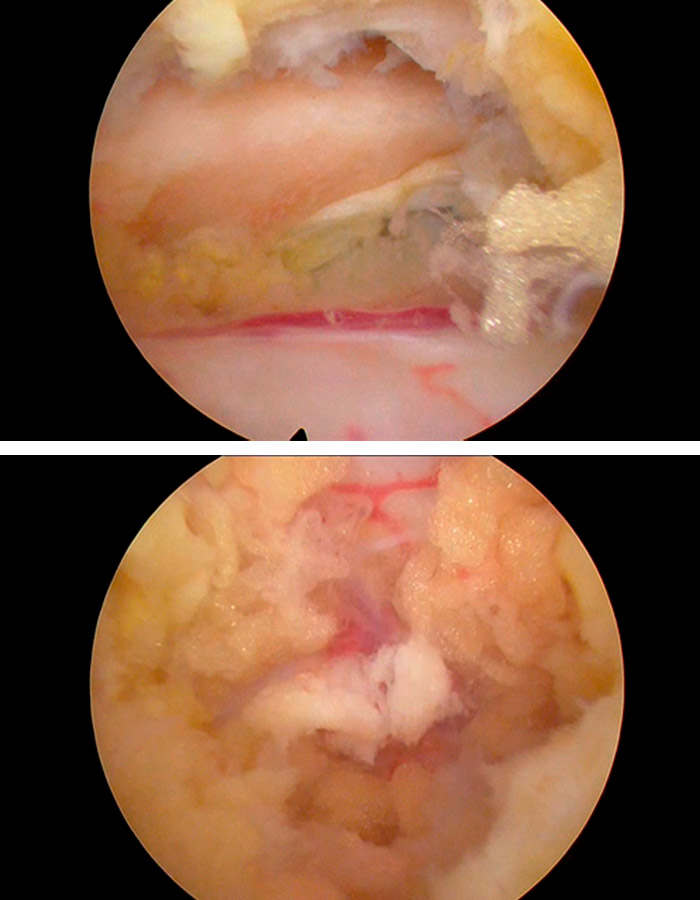

Comenzamos la operación realizando un abordaje interlaminar posterior con una aguja guía que nos ayuda a acceder al ligamento amarillo de forma bilateral.

Una vez hemos ubicado la zona en la que vamos a trabajar se realizan hemilaminectomías superiores también bilateralmente. Este proceso debemos hacerlo hasta haber comprobado la adeucada liberaicón del canal y de las estructuras neurológicas que antes estaban comprometidas.